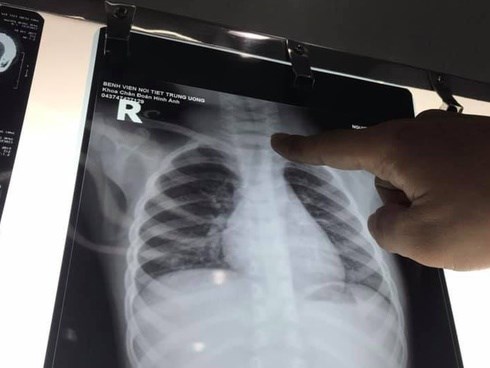

Một ca bệnh hiếm gặp tại Bệnh viện nội tiết Trung ương là trường hợp 5 chị em trong gia đình cùng mắc bệnh lý tuyến giáp, trong đó 2/5 người đã được chẩn đoán mắc ung thư.

Bệnh nhân nhập viện trong tình trạng rất nặng do viêm phổi, đường thở thường xuyên bị tắc nghẽn do dịch tiết, có những khi bão hòa oxy xuống quá thấp bệnh nhân tím tái phải cấp cứu, nếu không được khai thông đường thở kịp thời bệnh nhân sẽ tử vong.